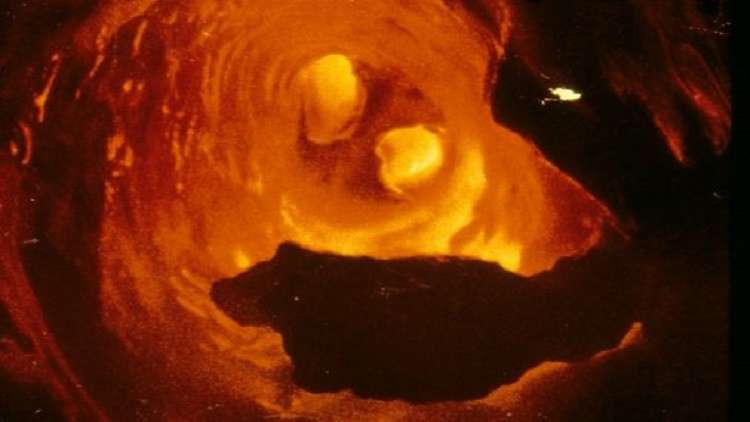

ووفقا لإحصائيات منظمة الصحة العالمية، يعد مرض تصلب الشرايين وأمراض القلب الأخرى المرافقة أحد الأسباب الرئيسية لتطور النوبات القلبية، وبالتالي الوفيات في معظم دول العالم، حيث يبدأ هذا المرض عادة بتراكم لويحات الكوليسترول على جدران الشرايين وبعد مضي فترة يزداد سمك هذه الجدران وتفقد مرونتها.